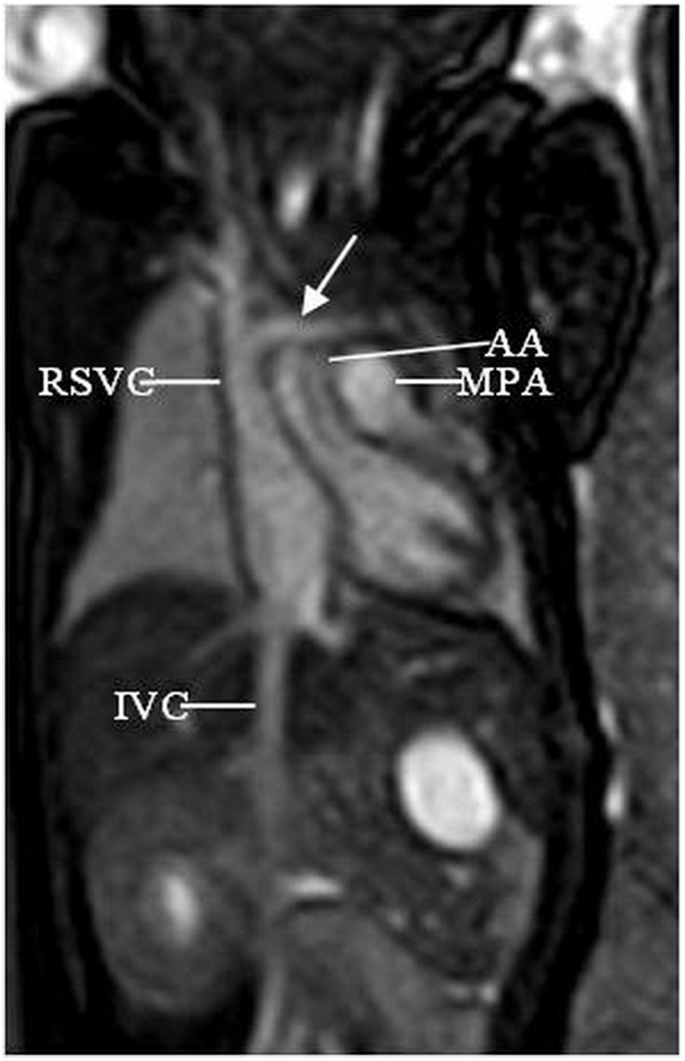

Mr Imaging Of Subaortic And Retroesophageal Anomalous